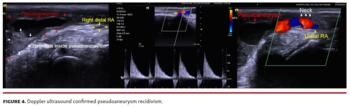

Six days later, she noticed subtle and rapidly progressive wrist, hand, and finger swelling, with pain, ecchymosis, and movement limitation. Physical examination evidenced pulsatile mass, thrill, and murmur, compatible with pseudoaneurysm (Figure 1). Doppler ultrasound (US) evidenced a huge cavity with whirlwind flow and spontaneous contrast communicating with the right distal radial artery (RA) (Video 1). After continuous 30-minute US-guided pseudoaneurysm’s neck compression (Figure 2), no pulsatile mass, thrill, murmur, whirlwind flow, or Doppler pulses were detected. One-week follow-up evidenced recurrence of pulsatile mass (Video 2), thrill, and murmur, compatible with pseudoaneurysm recidivism (Figure 3), confirmed by Doppler US (Figure 4; Videos 3 and 4). Following pseudoaneurysm neck precise location, a TR band was placed and inflated with 20 mL of air (Figure 5, Video 5). After 4 hours, Doppler US showed proximal and distal RA patency, absent flow, and complete resolution of the initial pulsatile cavity (Figure 6, Video 6). During TR band inflation and after its removal, pulse oximetry in all digits was ≥95% (Figure 7). Physical examination and Doppler US at 30 and at 120 days (Figure 8) after index procedures corroborated pseudoaneurysm resolution.